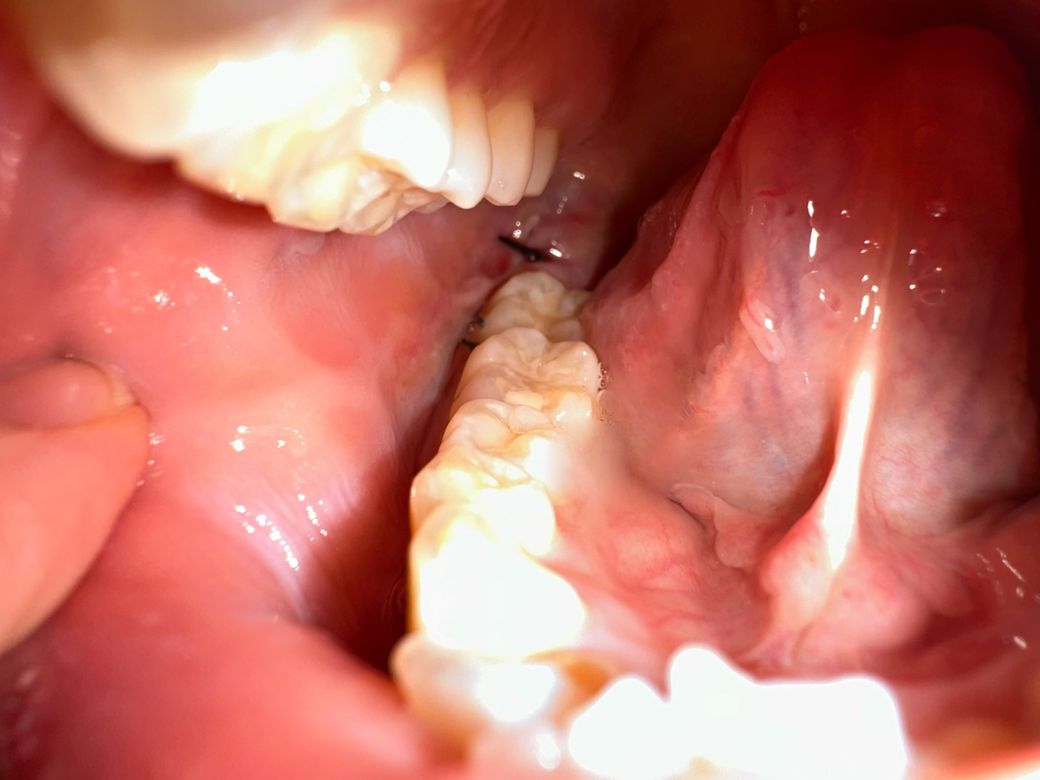

매복사랑니 잘 아물고 있는지 봐주실 수 있을까요

지금 뽑은지는 4일차입니다 이런 상태인데 잘 아물고 있는지 모르겠고 사람들마다 원래 실밥은 좀 다르나요 ?̊̈ 제 실밥만 이런가 싶어서요 잘 아물고 있는지 드라이소켓은 없는지 궁금합니더 지금 현재 좀 염증이 차있어거 턱이랑 볼쪽이 멍울처럼 딱딱하고 많이 부어있어요 ㅠㅠㅠ 괜찮은거겠죠? 치과에 가서 염증이 차있다고 하면 뭐 치료법이 따로 있나요? 입이 잘 안벌려지는건 염증때문일까요

• 1번 째 사진

봉합상태도 굉장히 좋고 염증소견도 없어보입니다.

발치후에 많이 붓고 아플 수 있는데요 때에따라 환자분처럼 입이 안벌어지기도 하지만 대부분 실밥을 풀 때 쯤에는 많이 호전이 됩니다.

그리고 발치후에 볼쪽을 눌러봤을때 덩어리처럼 단단한게 만져지는 경우도 있는데 상처가 나면 흉터가 생기는 것 처럼 안쪽에도 흉터가 생겨서 그렇다고 생각하시면 되는데요. 보통 시간이 지나면 점차 옅어집니다.